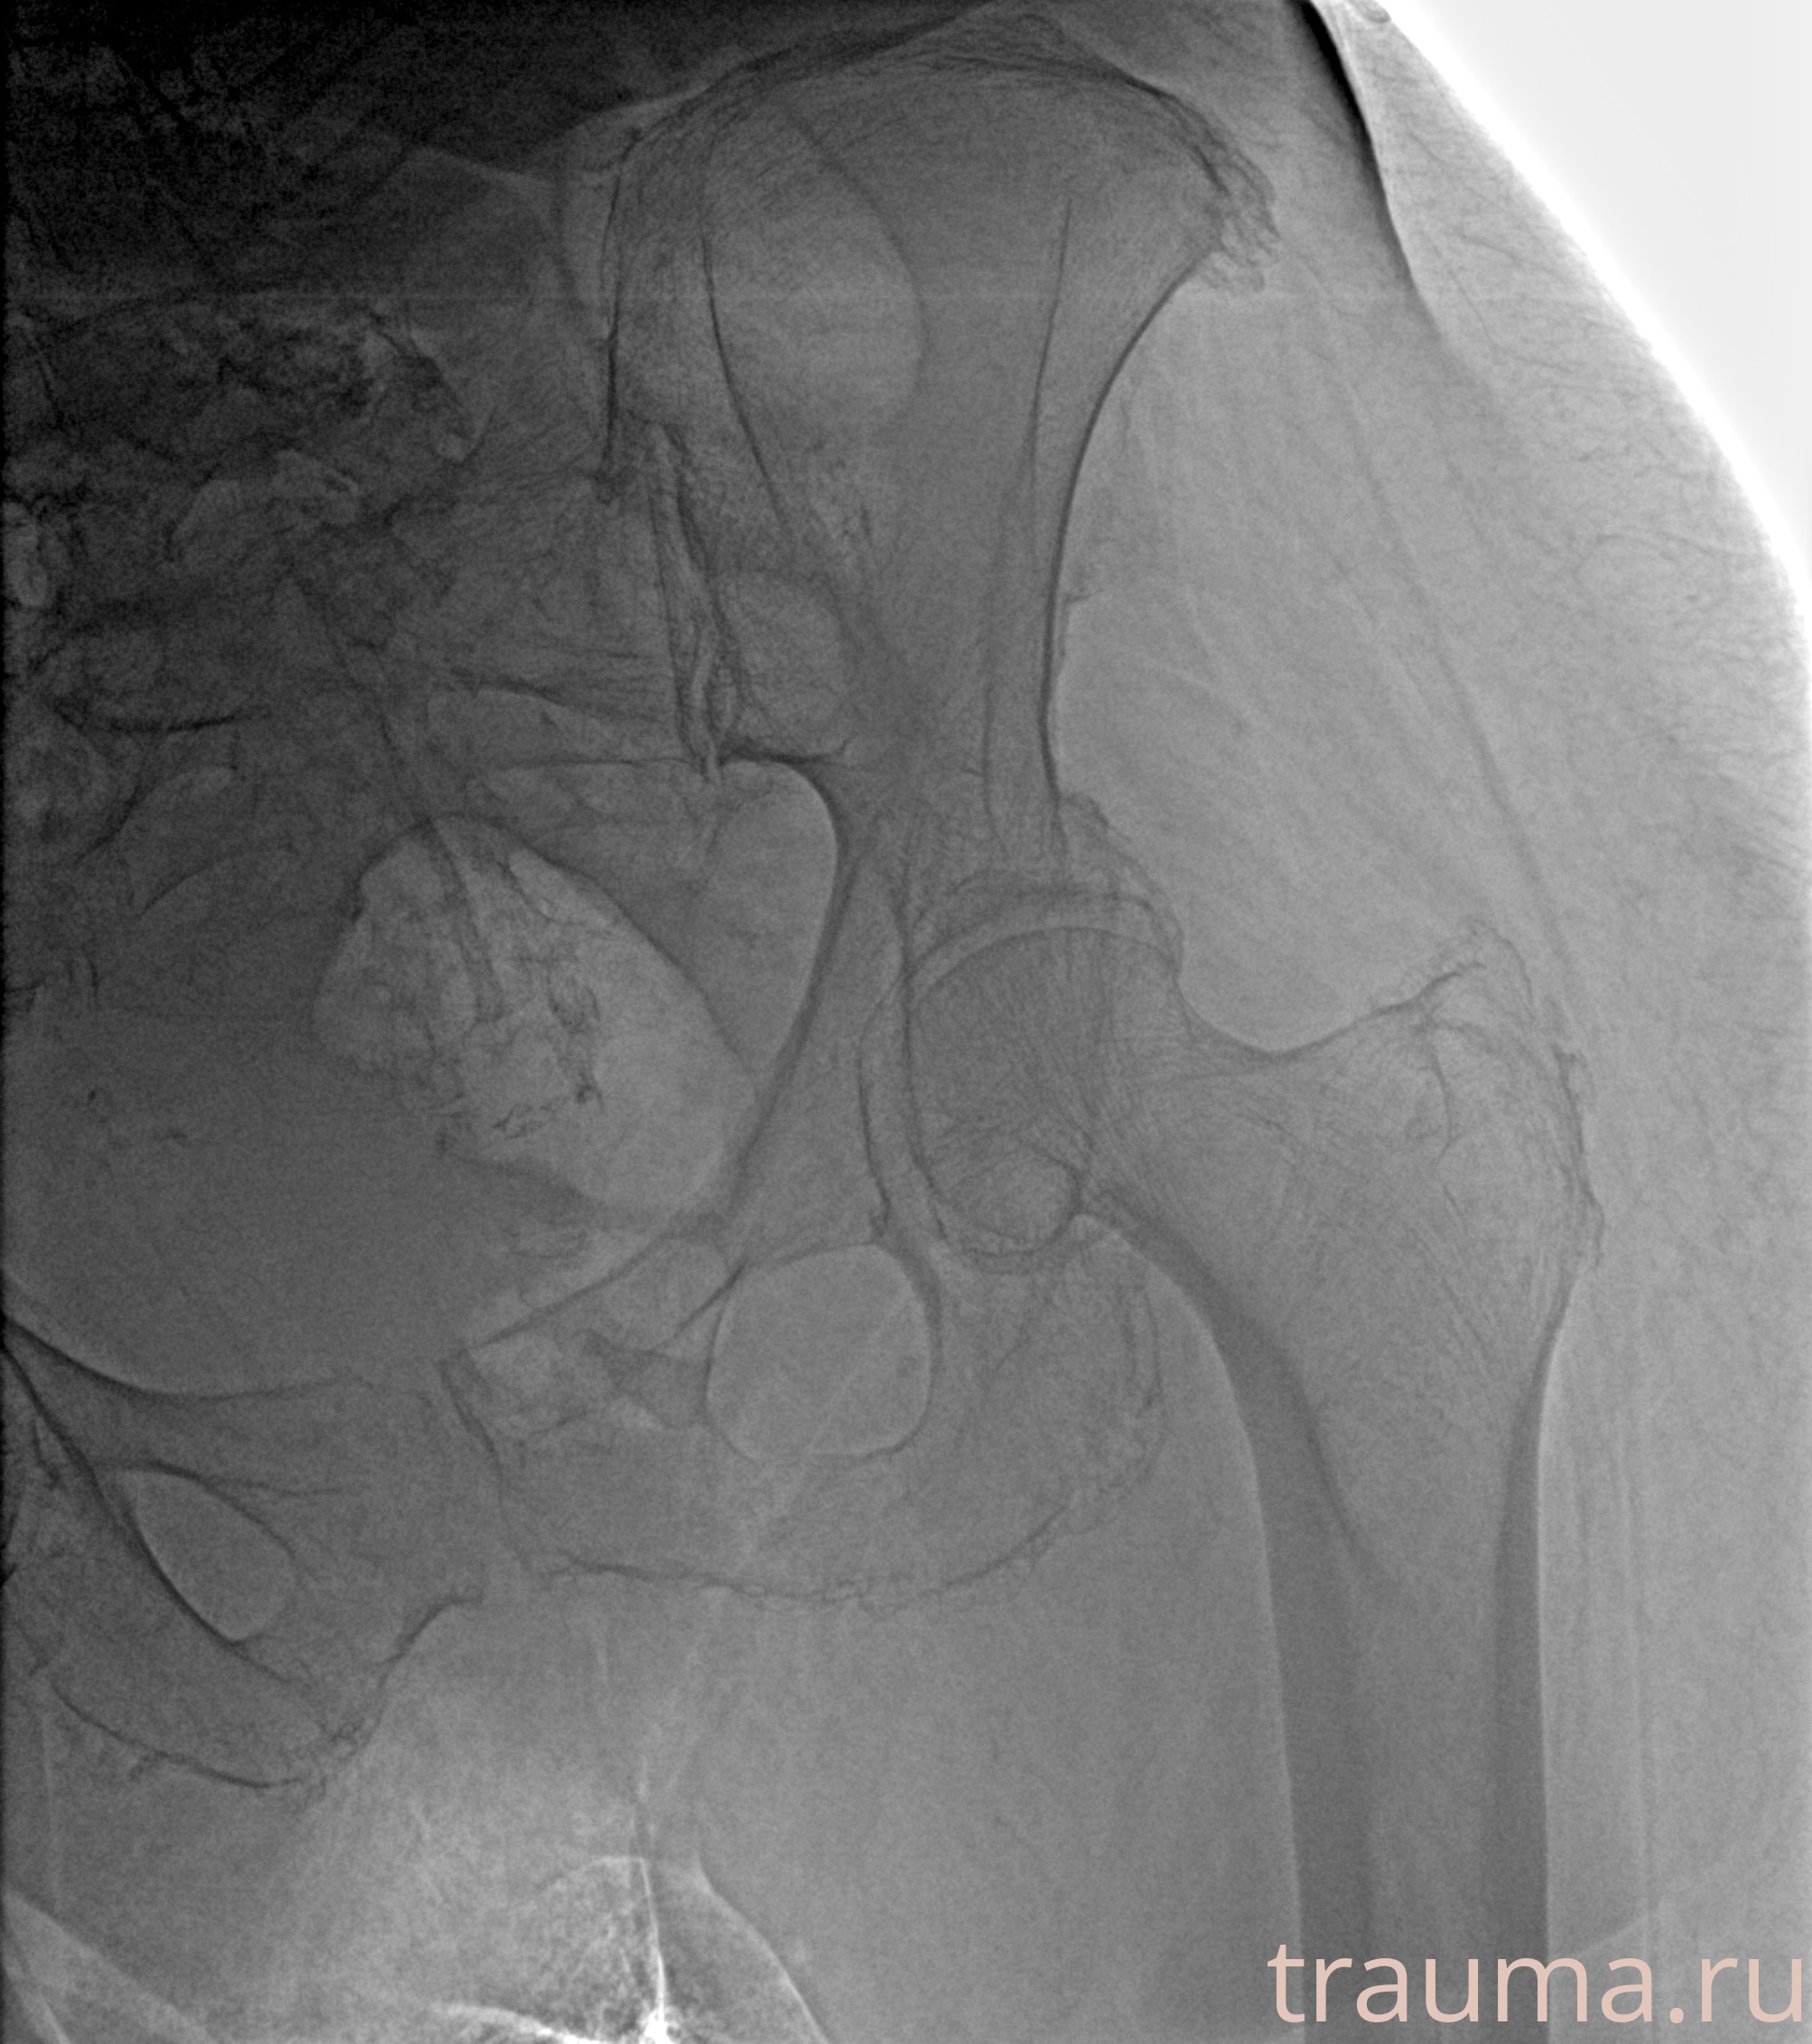

Рентгенограммы

Рентген на дому: по вашему адресу приезжает врач-рентгенолог, травматолог-ортопед с мобильным рентгеновским аппаратом, проводит диагностику травмы или заболевания, делает необходимые рентгенограммы, дает рекомендации по дальнейшему лечению. Получить качественные снимки в домашних условиях возможно благодаря уникальной методике, разработанной МосРентген Центром для института  Склифосовского